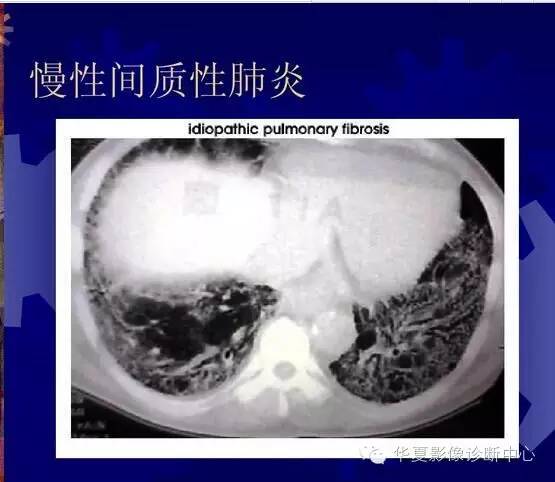

间质性肺炎

以肺间质为主的炎症,可由细菌、支原体、衣原体、病毒或肺孢子菌等引起。累及支气管壁以及支气管周围,有肺泡壁增生及间质水肿,因病变仅在肺间质,故呼吸道症状较轻,异常体征较少。X线通常表现为一侧或双侧肺下部的不规则条索状阴影,从肺门向外伸展,可呈网状,其间可有小片肺不张阴影。